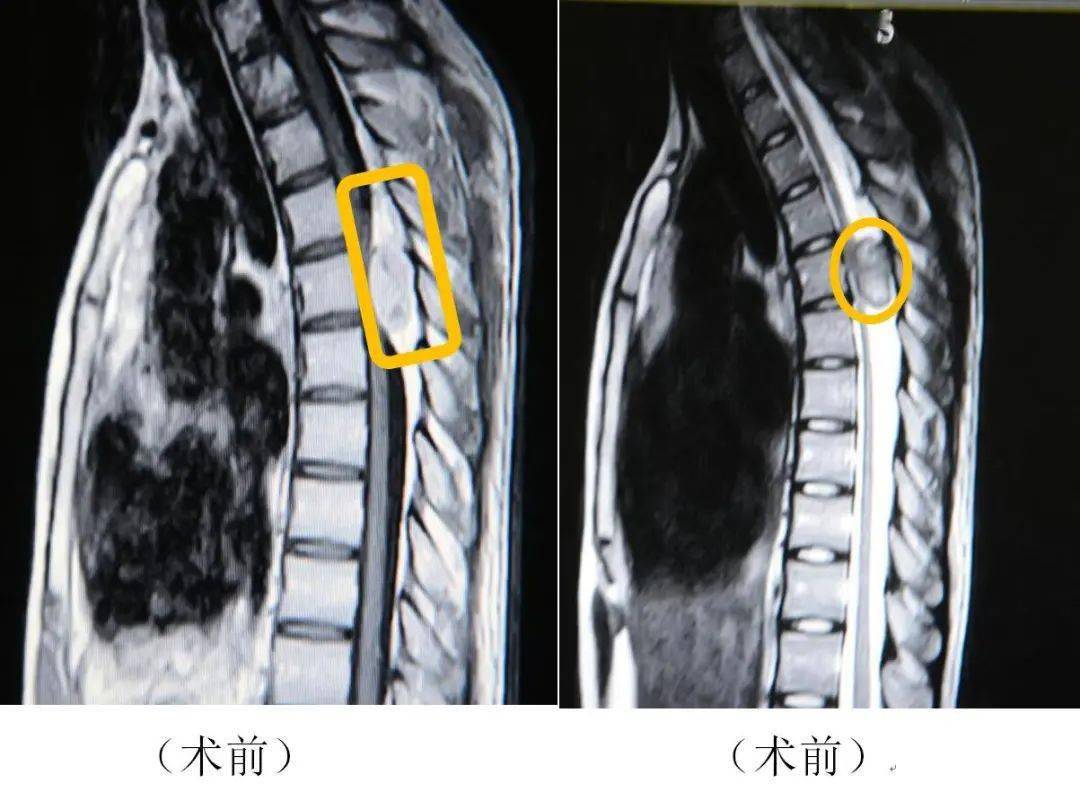

典型病例胸椎椎管内脊膜瘤

图片尺寸1094x713